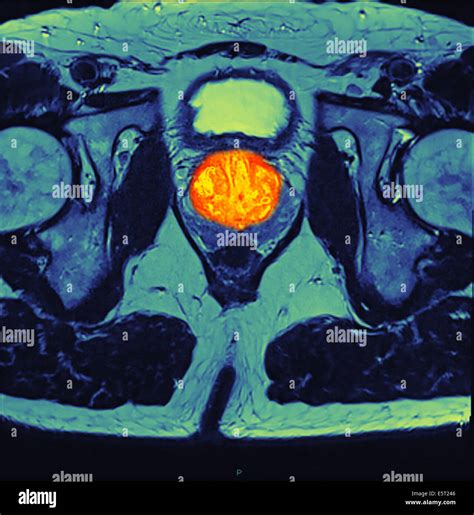

• Multiparametric MRI (mpMRI): This technique combines multiple MRI sequences, including T2-weighted imaging, diffusion-weighted imaging (DWI), and dynamic contrast-enhanced (DCE) imaging, to provide a comprehensive evaluation of the prostate.

• Prostate Imaging Reporting and Data System (PI-RADS): This standardized reporting system helps radiologists interpret MRI findings and classify the likelihood of clinically significant prostate cancer.

• Artificial Intelligence (AI): AI algorithms are being developed to assist in the interpretation of MRI images, potentially improving the detection and characterization of prostate cancer.

• Molecular Imaging: New contrast agents and molecular imaging techniques are being explored to provide more detailed information about the biological characteristics of prostate tumors.